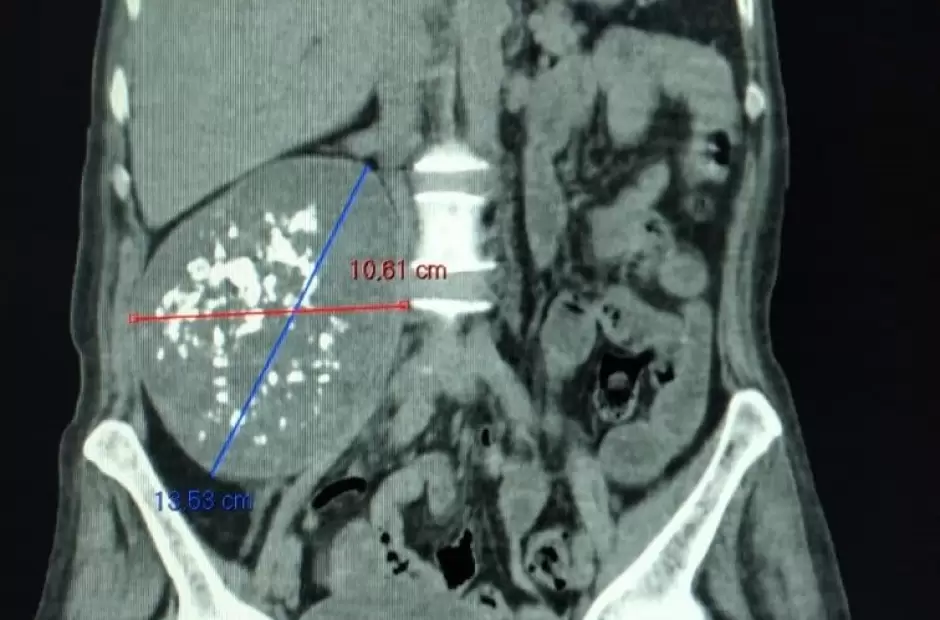

La exégesis fue sobre una masa tumoral de 10.61 x 13.50 cm. Los profesionales que intervinieron a la mujer de 58 años, marcaron que esta evoluciona y está compensada. La cirugía fue realizada por el equipo de Cirugía Oncológica y de Cabeza y Cuello, de reciente creación, y grandes logros a la fecha.

El equipo de Cirugía Oncológica y de Cabeza y Cuello del Hospital “San Juan Bautista”, encabezó este lunes, de manera exitosa, una intervención de gran envergadura, por medio de la cual se extirpó una masa tumoral de 10.61 x 13.50 cm. Los profesionales que intervinieron a la mujer de 58 años marcaron que esta evoluciona y está compensada. La cirugía fue realizada por el equipo de Cirugía Oncológica y de Cabeza y Cuello, de reciente creación, y grandes logros a la fecha. La cirugía se realizó sobre una paciente de 58 años procedente del interior de la provincia; la cual este martes se encontraba con buena evolución, compensada y bajo los cuidados de la Unidad Coronaria del Hospital.

“Ni bien recibimos a la paciente, hace una semana atrás, la compensamos y tomamos la decisión quirúrgica dada la necesidad de realizar cuanto antes la exéresis del tumor retroperitoneal paravertebral gigante que presentaba. Esta lesión se alojaba en todo el hemiabdomen y retroperitoneo derecho de la paciente, involucrando grandes vasos sanguíneos del colon, riñón y ureter, por lo que requerimos de la participación activa del Servicio de Cirugía Vascular”, destacó el Dr. Santiago Ravetti, Jefe del Servicio de Cirugía Oncológica y de Cabeza y Cuello.